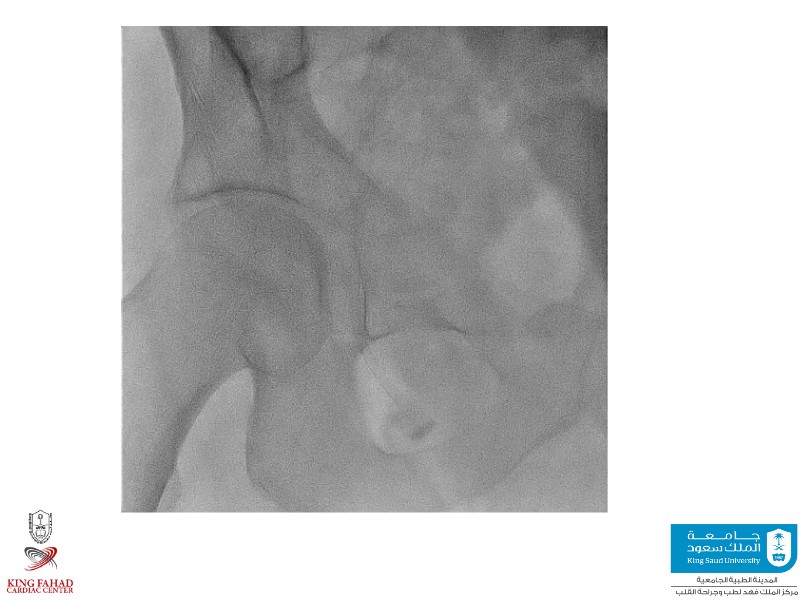

This session helps you anticipate and address complex scenarios such as mitral valve-in-valve, TAV-in-SAV, and valve-in-valve-in-valve procedures. Learn from expert case discussions that explore procedural strategies, technical challenges, and best practices to optimize outcomes in redo structural heart interventions.